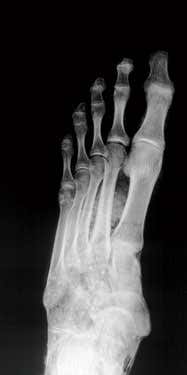

Wrong foot, right conclusion? Everett Collection/Rex Features

Connolly knew that the X-ray of the left foot appeared in a book Harrison had contributed to – Chronicle: Essays from ten years of television archaeology – written to accompany a TV documentary. New Scientist tracked down the book and the image shows a healthy foot.

Bob Read/University of Liverpool